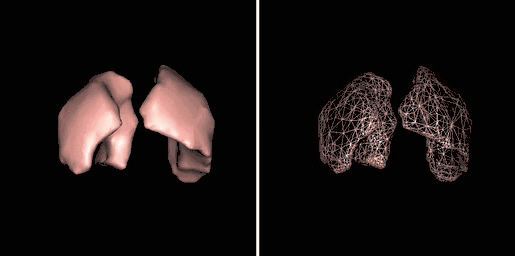

Surface rendering is also referred to as Shaded Surface Display (SSD) and involves generating surfaces from regions with similar voxel values in the 3D data as illustrated by the SPECT lung-perfusion scan shown in the left panel below:

The process involves the display of surfaces which might potentially exist within the 3D voxel data on the basis that the edges of objects can be expected to have similar voxel values. One approach is to use a grey-level thresholding technique where voxels are extracted once a threshold value is encountered in the line of the projection – see the following diagram. Triangles are then used to tesselate the extracted voxels, as shown in the right panel of the figure above – and the triangles are filled using a constant value with shading applied on the basis of simulating the effects of a fixed virtual light source – as shown in the left panel above.